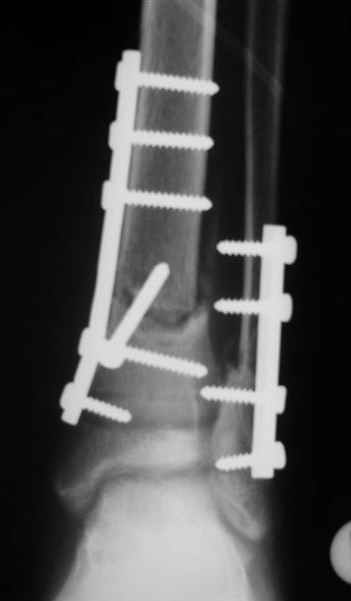

Помятуя наш недавний разговор о фиксации м.б. кост, высылаю послеоперационные картинки..

Напомню- разбирали случай 17 летнего молодого человека перелом дист тиб.фиб. хирургия после 3 недель с момента травмы( безуспешные попытки закрытой репозиции) Раны заживают первичным натяжением, занимается физиотерапией, пока никаких проблем не наблюдается

Согласный я с тобой:-)) есть остаточная вальгусная деформация (по снимку видно перекрывание дист. фрагментом б.б по латеральной поверхности проксимальноо фагмента на 2-3 мм и наружная лодыжка репонирована с укорочением, судя по прямой проекции. Необходимость использования интраоперационно дистрактора была бы оправдана (вручную было непросто *вытянуть* дистальный отломок.)

На мой взгляд, Ваша демонстрация неожиданно добавила перцу. Если память мне не изменяет, я говорил об отсутствии показаний к остеосинтезу малоберцовой.

Сейчас можно заикнуться о вредности этой манипуляции с точки зрения риска фиксации в неправильном положении, как это получилось у Вашего пациента. Сначала фиксировали большеберцовую, и надо было на этом остановиться, ин май хамбл опиньон. Потом при закручивании винтов на мощнейшей второй пластине сустав увело на вальгус. С учетом того, что пацану всего 17, я бы удалил пластину с малоберцовой и попытался тем или иным способом устранить смещение, пока не срослось.

Все так и не совсем - последовательность процедуры( я уже, кажется, упоминал)открыл зону перелома б.б., оценил мобильность фрагментов при очевидном смещении - отрепонировать вручную не получилось и понятна причина. Открыл область перелома м.б. отрепонировал( как мне показалось вполне адекватно) и фиксировал пластиной. ПРи ревизии зоны перелома б.б. положение фрагментов улучшилось, но сохранялось остаточное смещение дистального фрагмента кпереди хоть и незначительное, которое устранил и фиксировал межфрагментарным винтом, далее пластина. Конечно, следовало интраоперационно проконтролировать РГ, откровенно говоря, не ожидал, что постоп контроль будет так выглядить, показалось , что достигнутая репозиция вполне адекватна.....